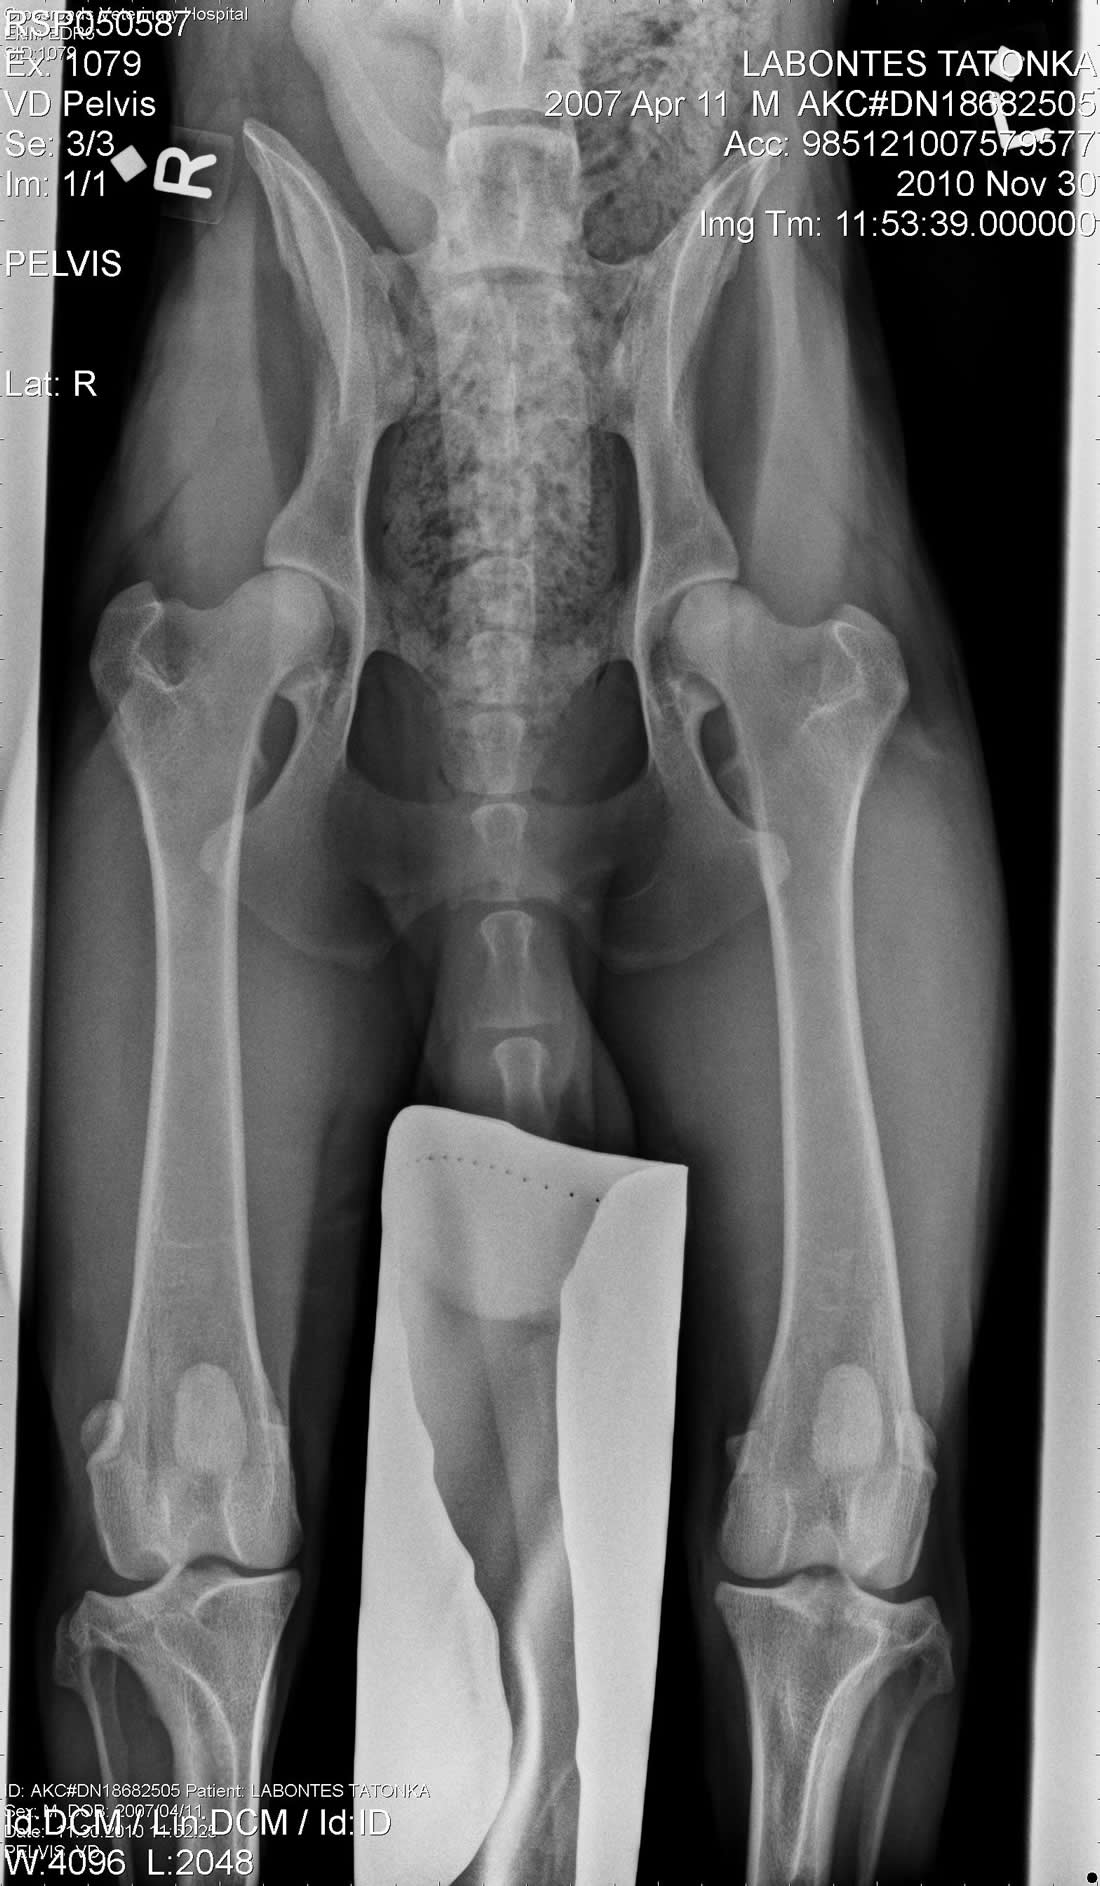

Hip X-Ray